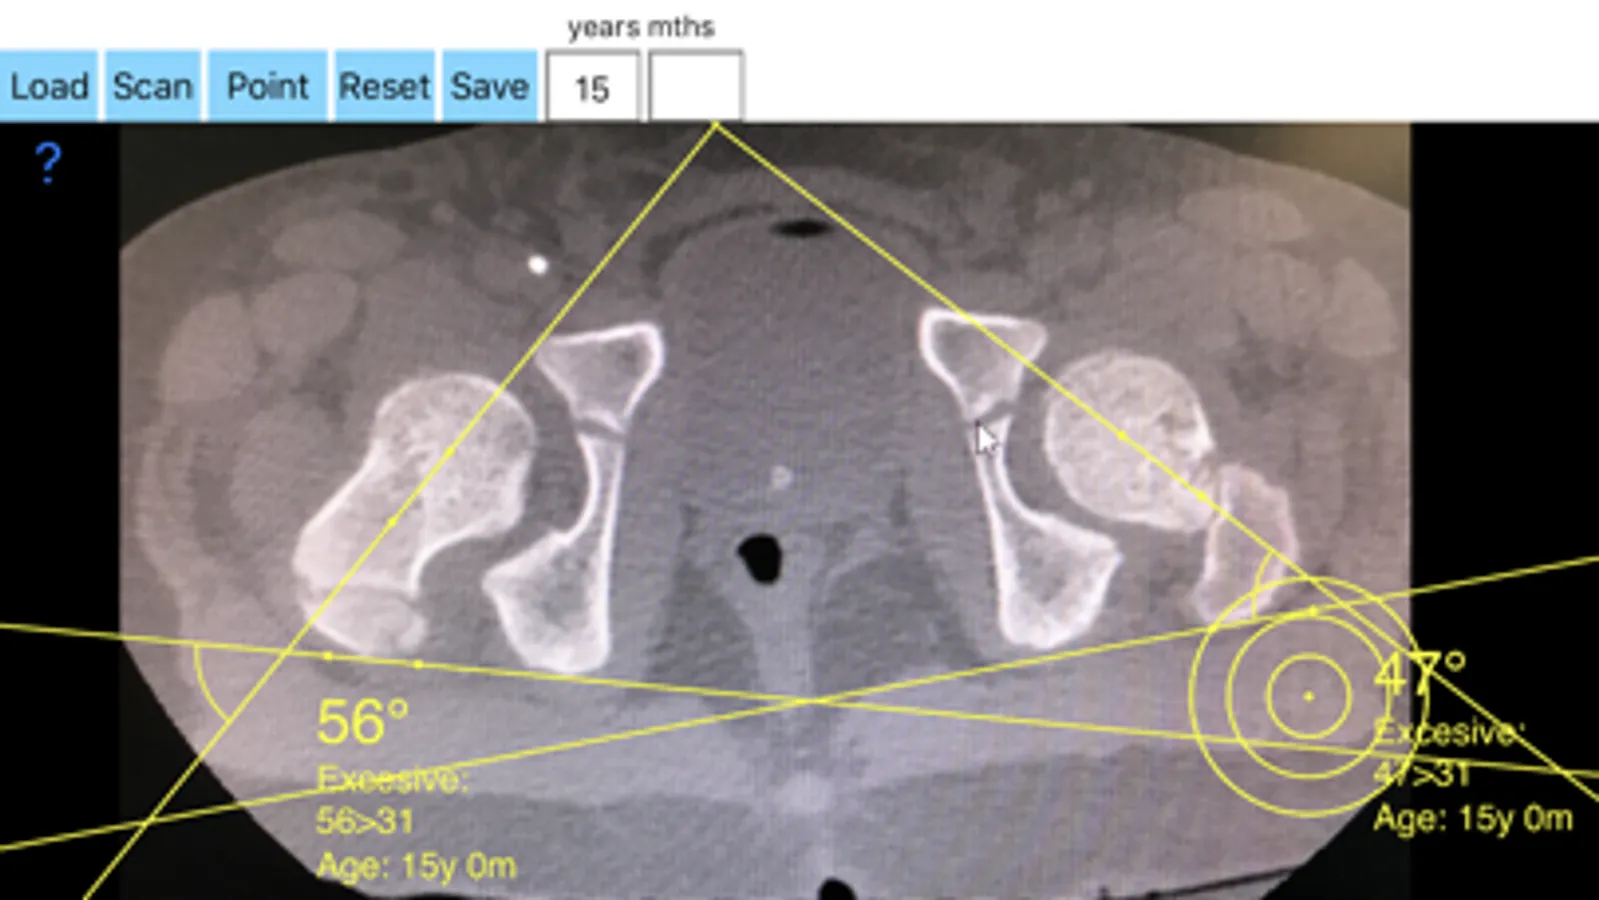

-By marking few points at the image of X-ray, the App calculates and offers a very convenient way to determine the most accurate possibly way at once.

-Save the planned images, for later review or consultation.The measured values are compared by normal reference databases according to age of the patient and help decide what are pathologic or normal.

In a busy everyday practice, the examiner have to draw lines in X-rays or in clinical settings, this it is time consuming and cumbersome. Accessory instruments like protractors, hinged goniometers, well sharped pencils, rulers or even transparent papers must be available. The app offers a very convenient and accurate way to perform most common radiographic measurements in a blink of an eye in front of your screen. The build in feature of the app, allows results to be categorized ( increased anterversion, excessive anteversion, decreased anteversion, or retroversion) according patient’s age by comparing the data with normal reference database, this feature may help decide what could be considered normal or pathologic.